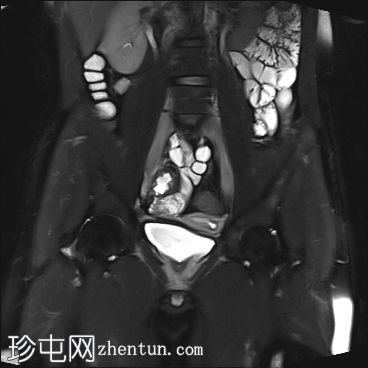

MRI

冠状位

STIR

MRI图像显示子宫和睾丸。子宫内膜腔开口于前列腺尿道。

患者有双侧隐睾病史。CT和MRI图像显示发育良好的子宫和两个睾丸,均位于盆腔内。子宫内膜腔开口于前列腺尿道。

该患者表型为男性,阴茎发育良好。精液分析显示无精子症。结合影像学检查结果,最可能的诊断是持续性苗勒氏管综合征。这是一种男性假两性畸形,由子宫内抗苗勒氏管激素(AMH)分泌不足引起。AMH或其信号通路的缺乏导致苗勒氏管衍生结构的持续发育。